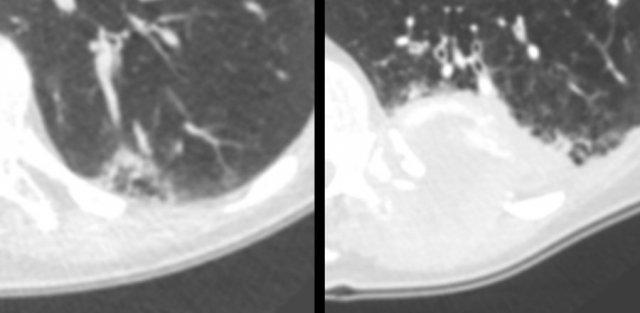

Đây là một ví dụ khác về ung thư phổi dạng nang biểu hiện quá trình ‘đặc hóa’, từ tổn thương tiền thân ban đầu với dày thành không đều kín đáo tiến triển thành một khối đặc tại thời điểm chẩn đoán.

Các hình ảnh minh họa một ví dụ khác về ung thư phổi dạng nang biểu hiện quá trình ‘đặc hóa’.